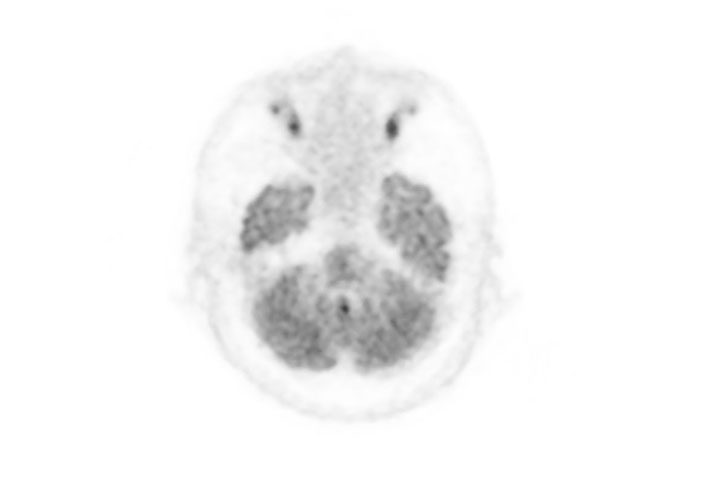

Head / Case2 : FDG

Courtesy : Kindai University Hospital

- Imaging protocol

- Injected dose: 3.29 MBq/kg, 18F-FDG

- Uptake time: 38 minutes

- Scan time: 30 minutes